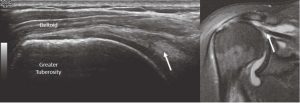

The supraspinatus tendon’s normal appearance has a curved contour deep to the deltoid, and the greater tuberosity has a notch at the insertion. It is at this notch that it is common to see anisotropy, which should not be confused with a tear (Figure 7).

Full-thickness tearing is seen with fiber disruption, fluid collection and tendon retraction similar to full-thickness tearing in the Achilles (or any) tendon (Figure 8). The anatomy can be compared to MRI.

Partial tearing can be more difficult to see with a smaller area of fluid collection and fiber disruption without tendon retraction. It is common to see cortical defects deep to tendon tears as a secondary sign of tearing (Figure 9).